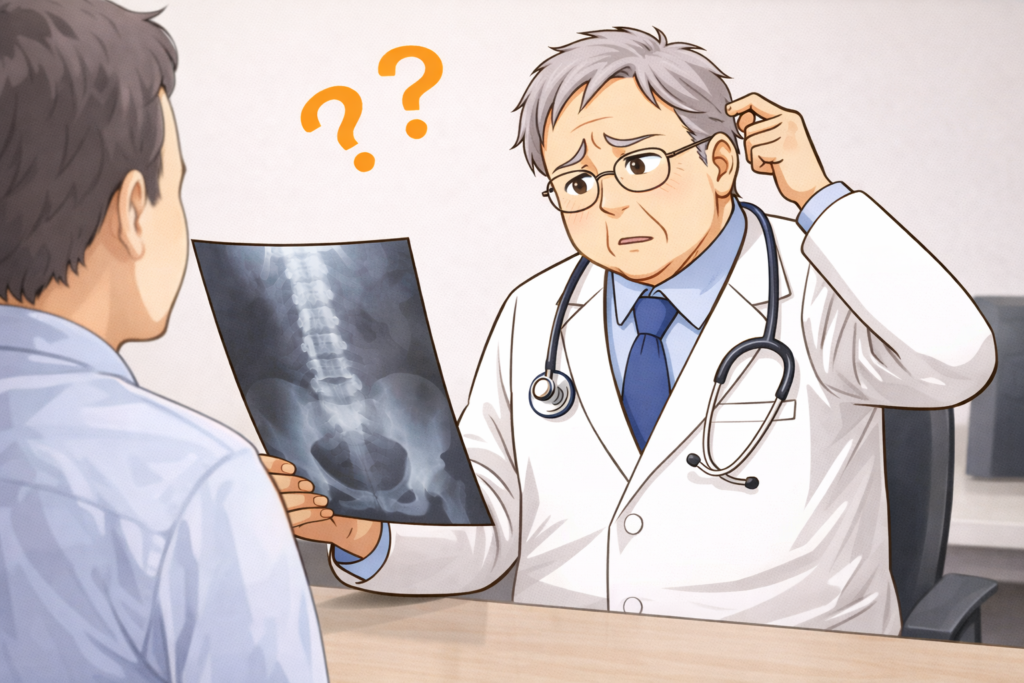

仙腸関節性腰痛は、レントゲンやMRIでははっきり写らないことが多いため、体の動かし方や押したときの痛みを確認して判断します。

- レントゲンやMRIでは大きな異常が見つかりにくく、「原因がはっきりしない腰痛」として扱われやすい。

仙腸関節はレントゲンやMRIに写りにくい関節のため靭帯や関節包が、わずかに引っ張られた状態で少し伸びただけでも痛みのセンサーが反応する特性があり痛みが出ることがあり、画像が正常でも仙腸関節に由来する痛みは多くあります。